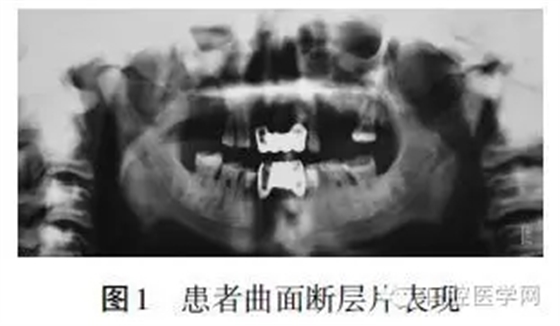

(2)曲面斷層片示:上頜骨低密度影,小塊死骨形成,與周圍骨界限清楚(圖1)。